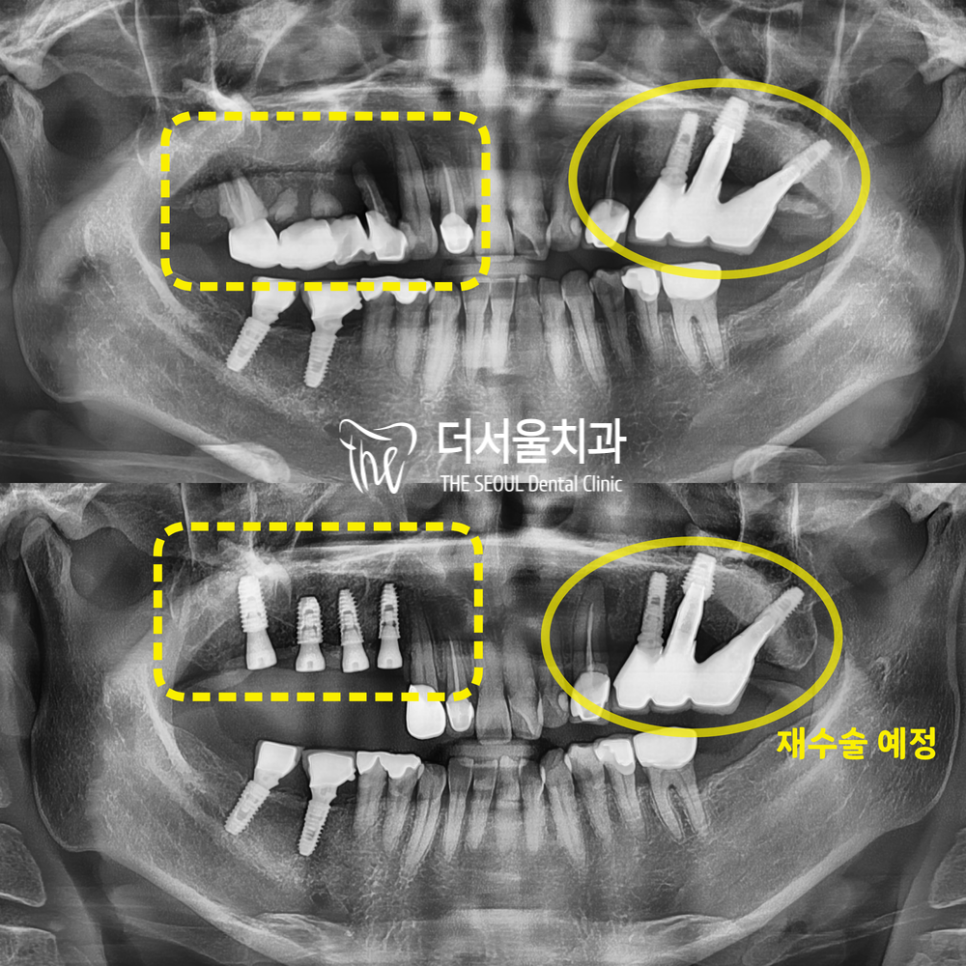

안녕하세요, 글쓴이 박현준 원장입니다. 오늘은 상악동 거상술 및 뼈이식과, 같이 임플란트 수술을 진행했던 증례입니다. 아래 사진으로 바로 설명드릴게요.

안녕하십니까, 여러분! 더서울치과 박현준 원장입니다. 얼마 전, 이가 흔들려서 걱정이 된다며 다급한 모습으로 찾아오셨던 분이 계십니다. 오늘은 그분의